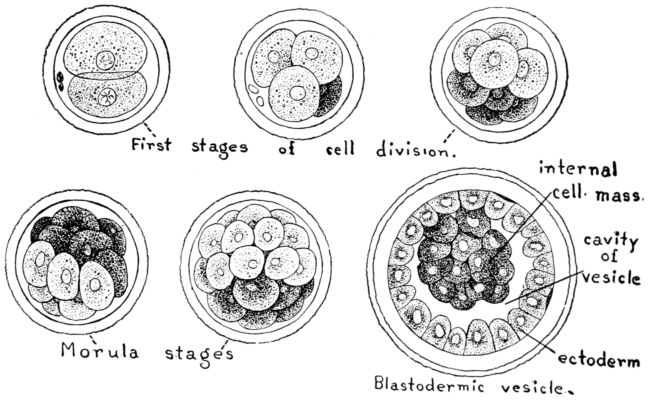

| 18. | Diagram of segmenting rabbit’s ovum | 65 |